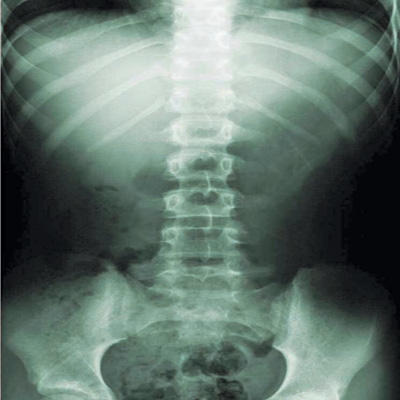

تقويم العمود الفقري طب يدوي مرجعي لمعالجة الظهر والمفاصل. يهدف إلى تشخيص الاضطرابات في الجهاز العضلي الهيكلي ومعالجتها والوقاية منها، لا سيما على مستوى العمود الفقري والأعضاء. العلاج فاعل في جميع الأعمار ويستفيد منه المسنون تحديداً.

للوقاية من ألم الظهر وتخفيف حدته في جميع الأعمار، يقترح قطاع تقويم العمود الفقري علاجاً كاملاً. فيرصد المعالج الاختلالات في العمود الفقري والاضطرابات في الجهاز العضلي الهيكلي ويعالجها بالتقنيات المناسبة: ضغوط خفيفة أو قوية تليها توصيات عن وضعيات الجسم السليمة.